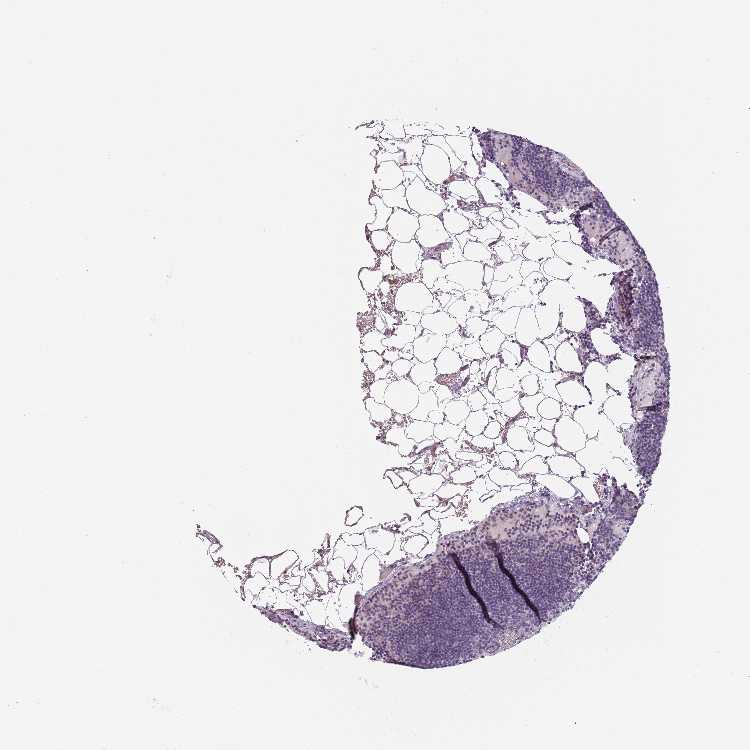

LYMPH NODE - Antibody stainingi

Antibody staining in the annotated cell types in the current human tissue is reported as not detected, low, medium, or high, based on conventional immunohistochemistry profiling in selected tissues. This score is based on the combination of the staining intensity and fraction of stained cells.

Each image is clickable and will lead to virtual microscopy that enables deeper exploration of all samples and also displays staining intensity scores, fraction scores and subcellular localization as well as patient and tissue information for each sample.

Antibody HPA046063

Non-germinal center cells Not detected